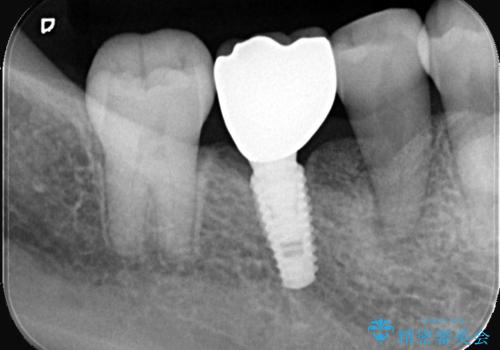

右下6番のインプラント治療: 5番の歯周組織が安定し、7番の傾きが改善された後、失われた6番の部分にインプラントを埋入。周囲の歯と調和した被せ物を装着し、強固で自然な奥歯を再建しました。

この総合的な治療により、右下奥歯全体の歯周環境と咬み合わせが劇的に改善。患者様には、安定した咬み心地と、将来にわたって歯を長持ちさせる環境を獲得していただけました。